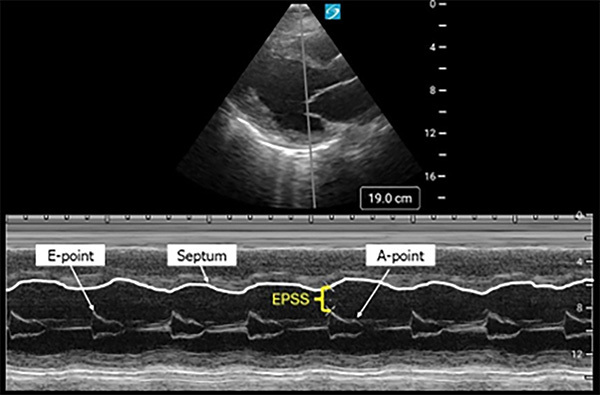

Measurement of E-point septal separation (EPSS) is another way to estimate the LVEF%. This measurement is taken in the PLAX view of the heart with the M-mode tracer over the distal tip of the anterior mitral valve leaflet (AMVL). The waveform created by movement of the AMVL creates two peaks. The larger peak is the E-point and corresponds to the maximal mitral valve opening during early diastole. The smaller peak is the A-point, which corresponds to the atrial contraction during later diastole. The distance between the E-point and the interventricular septum is the EPSS. (See Figure 5.)

Figure 5. Ultrasound Image of E-Point Septal Separation (EPSS) Taken in M-Mode |

![]() |

Source: Image used with permission from Youssef Annous, MD. |

Normally, there would be little separation between the E-point and the interventricular septum. Increasing EPSS is inversely associated with LVEF%. A study by McKaigney et al demonstrated that an EPSS of > 7 mm was 100% sensitive and 51.6% specific for severely reduced LVEF% (< 30%).67